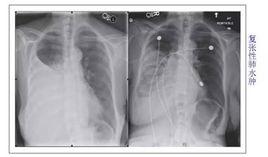

復張性肺水腫液中蛋白質含量高,與血漿中的蛋白比為0.73,而肺毛細血管嵌壓正常。多為單側發病,也可累及對側,臨床表現與心源性肺水腫十分相似,一般診斷並不困難。以下表現中的3項以上即可做出診斷。(1)有胸腔積液、積氣等肺受壓萎陷病史;(2)有胸腔引流或手術肺急性復張誘發;(3)肺復張後短時間出現呼吸困難的臨床表現,如劇烈咳嗽、咳出或吸出大量白色或粉紅色泡沫樣痰或液體,呼吸急促淺表;(4)患者單側或雙側肺有細小水泡音、心率增快;(5)若麻醉恢復期則表現自主呼吸淺快,氣管導管咳出或吸出泡沫樣痰或粉紅色液體;(6)SpO2早期不穩定,繼而持續下降;(7)影像學檢查患肺遍布點狀、片狀模糊陰影;(8)特殊檢查有血液濃縮,肺內分流,低氧血症,代謝性酸中毒等。